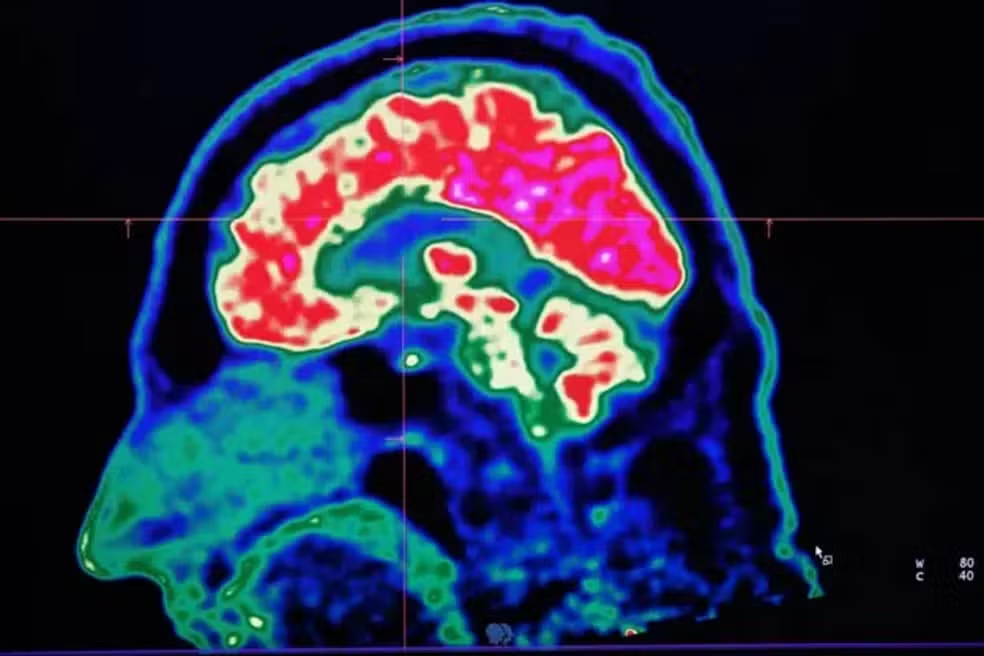

Mas o calor também pode alterar a forma como nosso cérebro funciona, nos deixando mais violentos, irritados e depressivos.

Assim, diante de um planeta que continua esquentando por causa das mudanças climáticas, qual impacto disso sobre o nosso cérebro?

O cérebro humano, em média, raramente ultrapassa 1°C acima da temperatura corporal.

Ainda assim, por ser um dos órgãos que mais consomem energia no nosso corpo, ele produz uma quantidade considerável de calor próprio enquanto pensamos, lembramos de informações e reagimos ao mundo ao nosso redor.

Isso significa que o corpo precisa trabalhar duro para manter o cérebro resfriado. A circulação sanguínea, por meio de uma complexa rede de vasos, ajuda a manter essa temperatura, levando embora o calor em excesso.

Isso é necessário porque as células cerebrais são extremamente sensíveis ao calor. E o funcionamento de algumas moléculas responsáveis por transmitir mensagens entre essas células também parece depender da temperatura, ou seja, elas param de trabalhar de forma eficiente se o cérebro estiver muito quente ou muito frio.

“Nós não compreendemos totalmente como os diferentes elementos desse quadro complexo são afetados” diz Sisodiya. “Mas podemos pensar nisso como um relógio cujos componentes deixem de funcionar em harmonia.”

Embora temperaturas extremas alterem a forma como nosso cérebro trabalha — podendo, por exemplo, afetar nossa capacidade de tomar decisões e nos levar a assumir mais riscos — quem tem alguma condição neurológica costuma ser mais gravemente impactado.